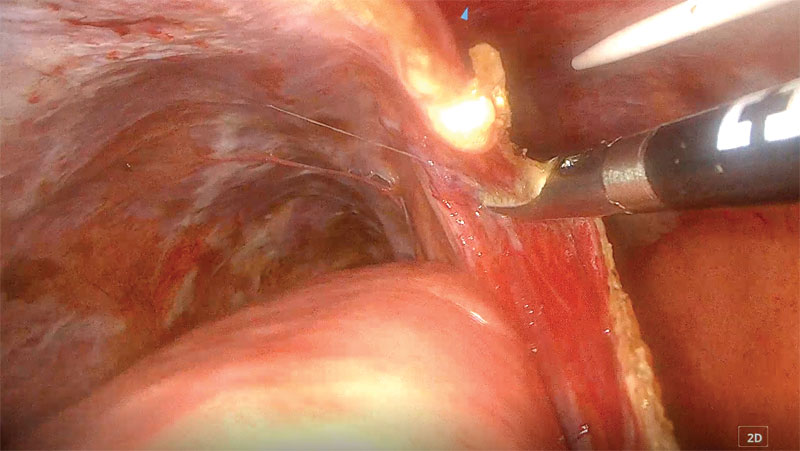

Once the thoracic duct has been identified, dissection immediately dorsal to the aorta is then performed to isolate the thoracic duct (Figure 9). A longitudinal incision is created dorsally to the aorta, carefully avoiding the intercostal arteries to prevent hemorrhage (Figure 10). If an intercostal artery is damaged, ligation can be performed using a vessel sealing device if necessary.

Figure 9. Thoracoscopic dissection is being performed on the thoracic duct. Photo courtesy Dr. Ashley Villatoro

Figure 10. Longitudinal incision created using J-hook cautery immediately dorsal to the aorta, between the intercostal arteries, to better dissect and access the thoracic duct.

Photo courtesy Dr. Ashley Villatoro